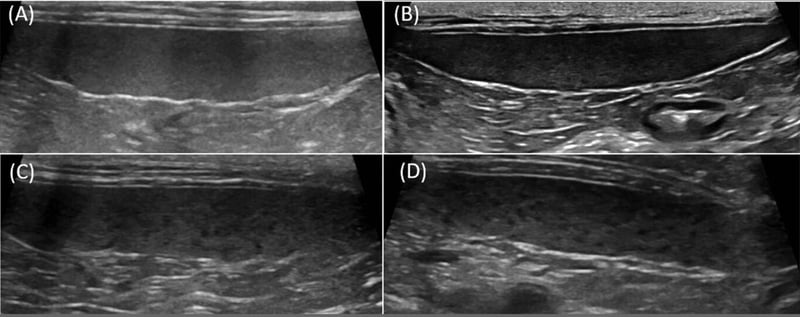

UltrasoundUltrasound